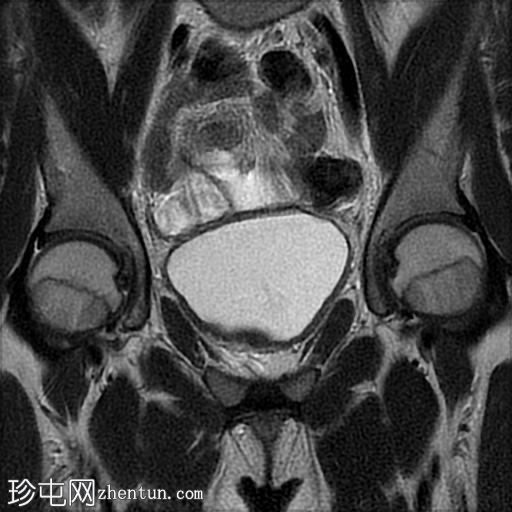

冠状位

T2加权像

脂肪抑制序列显示:

女性外生殖器

子宫、宫颈、阴道上2/3及卵巢缺失

双侧睾丸异位,沿腹股沟管清晰可见

MRI表现符合伴女性外生殖器的雄激素不敏感综合征(男性假两性畸形)。